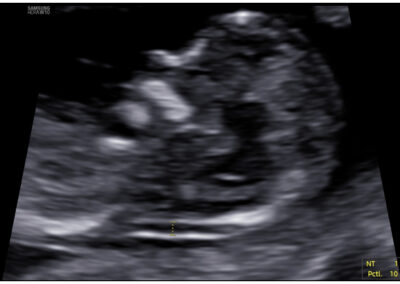

Vyšetření časného těhotenství NT screening Downova syndromu v 1.trimestru Screening vrozených vad ve 2. trimestru Screening ve 3. trimestru